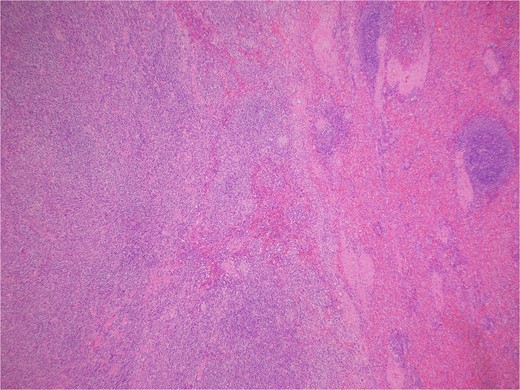

Histologic sections revealed spleen with partial effacement of tissue architecture by a well-circumscribed, nonencapsulated mass (Fig. 3) displaying mixed inflammatory elements, including scattered reactive-appearing lymphoid cells with a vague nodular appearance, plasma cells, histiocytes, and giant cells. Variably increased stromal/spindled cells were noted throughout (Fig. 4). The background splenic architecture appeared unremarkable.

A well-circumscribed, nonencapsulated mass displaying mixed inflammatory elements (hematoxylin & eosin 40X).